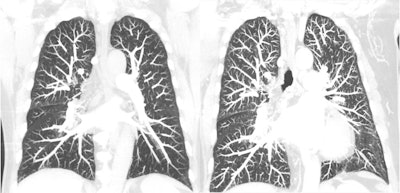

Various teams of researchers have reported that photon-counting CT performs well across a variety of applications, from visualizing multiple myeloma and cerebrospinal fluid (CSF) venous fistula (CVF) better than conventional CT to helping to better diagnose interstitial pneumonia. Other vendors have thrown their hats into the proverbial photon-counting CT ring as well: In March, NeuroLogica secured FDA clearance for its mobile CT system with photon-counting detectors, and Canon Medical Systems, GE Healthcare, and Philips have indicated they are at full throttle in their own photon-counting CT development.